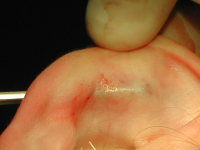

Область противозавитка и чаши освобождают от кожи и перихондрия через заушный разрез. Так как толщина и гибкость противозавитка не одинаковы по всей его длине, самая упругая нижняя часть нуждается в сквозном рассечении хряща для того, чтобы стало возможным его сгибание. Этот участок играет очень важную роль в формировании ушной раковины. Сквозной продольный разрез хряща, длина которого составляет примерно 1 см, производится в нижней части противозавитка. Через него вводятся изогнутые ножницы с неострыми кончиками, с помощью которых осуществляется отслойка мягких тканей передней поверхности в проекции противозавитка так, чтобы в сформированный туннель можно было поместить нож для хряща.

После введения в карман ножа вдоль проекции противозавитка, ранее обозначенной маркером, производятся несквозные параллельные насечки хряща. Данные манипуляции прекращаются тогда, когда хрящ перестает сопротивляться при сгибании и образует противозавиток нужной формы.

Введение в разрез хряща ножа для выполнения насечек на передней поверхности противозавитка